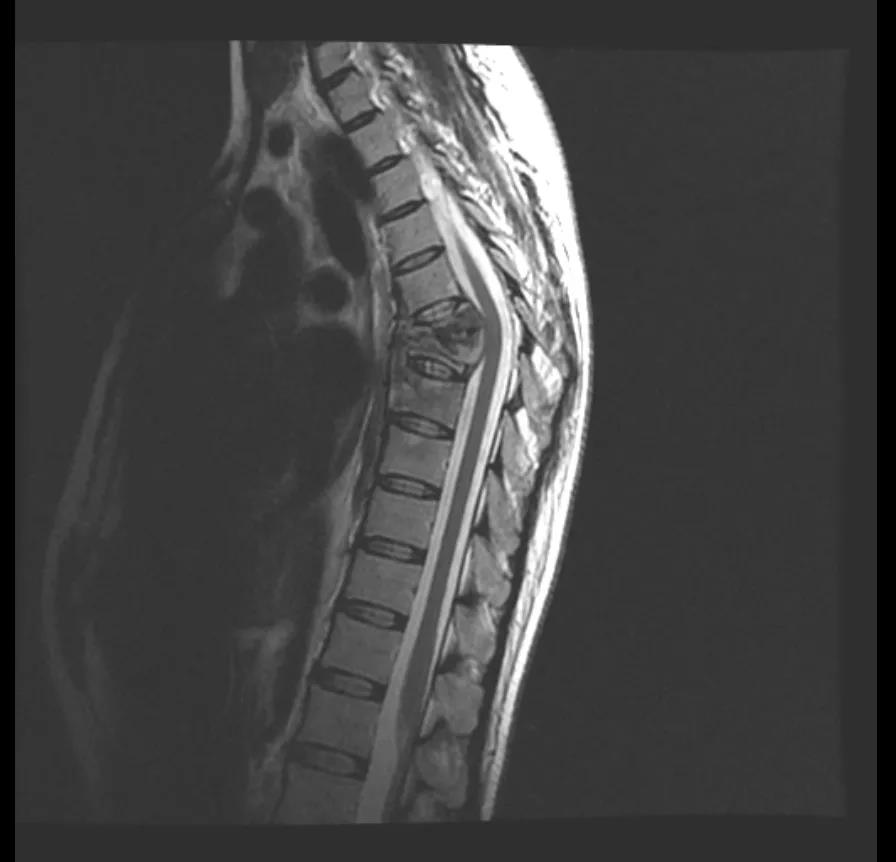

扎西来到成都新华医院骨科黄永红主任处就诊,CT核磁共振检查结果如黄主任所料扎西拉姆第6、7、8、9椎体被严重侵蚀,腰椎就好像被“吃掉了”;此外,椎体周围还形成了大量脓肿,对脊髓及神经造成压迫。

扎西的“脊椎结核”已经严重影响了脊柱的稳定性,“结核病灶在椎体内扩散,如不及时处理,会进一步侵犯脊椎椎体、椎管,压迫神经,进一步加重下肢乏力,甚至引起瘫痪、大小便失禁等后果”黄主任介绍。

手术必须尽快完成,但手术的难度也不小。由于结核病菌的侵蚀,扎西的脊椎体已经出现压缩塌陷、并压迫了椎管神经,手术需要在保护好脊髓和神经的前提下,切除病变的椎体;这个操作本身就存在非常高的神经损伤风险。